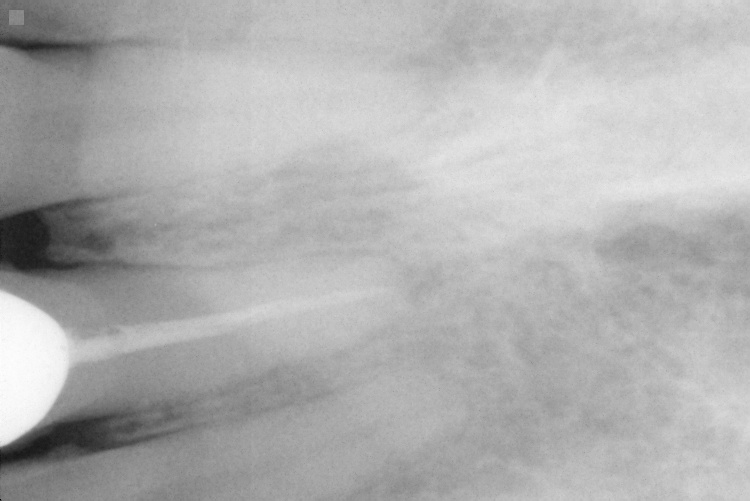

[PARENTDIR] Parent Directory - [IMG] IO000001.jpg 2020-07-28 14:17 77K [IMG] IO000002.jpg 2020-07-28 14:17 79K [IMG] IO000003.jpg 2020-07-28 14:17 82K